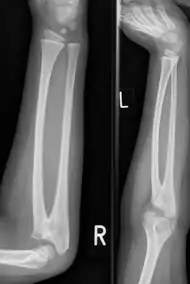

| Congenital radioulnar synostosis in a 7 year old boy | |